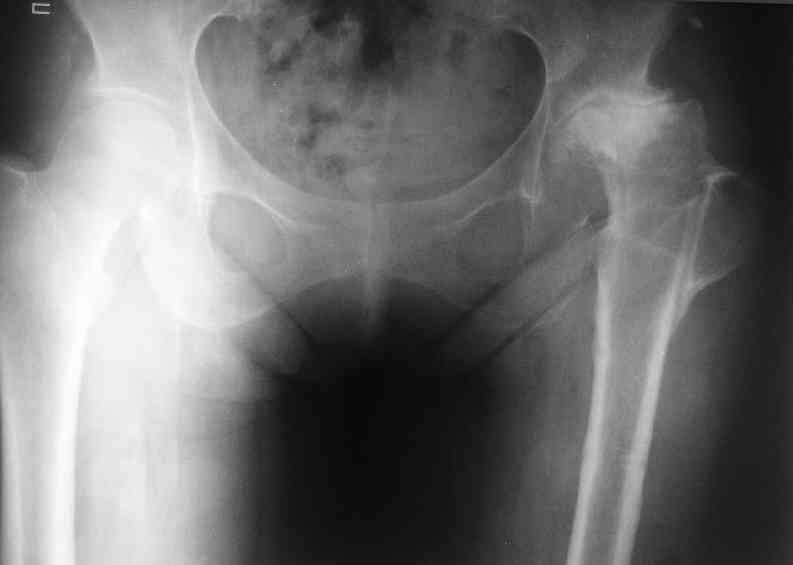

А за счет чего такое укорочение? По снимку не видно соответствующего дефекта. Ну плюс приводящая контрактура - но все равно как-то уж больно много. Может, сделать снимки и таза обзорный с обоими проксимальными отделами бедра, и коенный суставов с приложенной линейкой какой?

Судя по снимку, максимум истинное укорочение около 4 см, что может быть коррегировано интраоперационно. Вопрос в другом: куда ставить ацетабулярный компонент в истинную или во вновь сформированную ( впадина диспластичная).

Невозможно не согласиться с Анатолием, чтобы заниматься адекватным планированием как минимум прямая проекция таза должна быть сделана, как

максимум для оценки состояния мышц( насколько реально возможно низвести бедро) прямая проекция таза с тракцией за больную ногу.

The X ray that you provided does not show 8 cm of shortening. Perhaps you could send one showing the whole pelvis and proximal femurs.

I agree with Dr Eid's comments. The origin of the 8 cm leg length difference is a puzzle. Is this a clinical measurement? In that case contracture of the joint might affect the measurement. Can we see an AP pelvis to include both hip joints (including a calibration object with a known length) so that the difference in leg lengths that can be ascribed to the hip deformity and bony reabsorption can be measured. This sort of xray will help with templating for the TJR also. I would be very tempted to do a one stage procedure and accept some shortening. Shoe lifts should take care of a 3-4 cm difference.

До травмы проблем с ногой не было. Укорочения, болей и т.п. не отмечал. Сегодня перемерял укорочение - меньше 7 см намерять не

По уровню малых вертелов (с учетом рентгеновского увеличения) получается 5 см. Клинически ногу низвести путем тракции невозможно. Из движений - сгибание до 40*, остальные движения "символические".